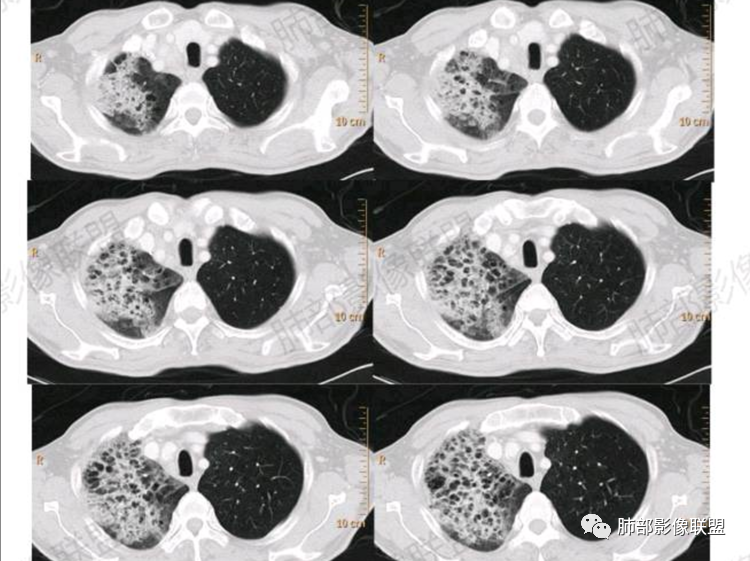

无明显肺气肿背景下右侧GGO+实变中见蜂窝征

实变区在胸膜下,部分边缘膨隆,凸向胸壁

2.影像显示右肺较广泛蜂窝样阴影,上肺及下肺为主,未见液平及重力分布趋势。其中上叶后段及下叶后基底段近胸膜下可见实性密度区,实性密度区强化明显,周边特征掩盖不清。

2.单肺或单肺叶蜂窝样阴影,CYFRA211增高等应当高度警惕恶性肿瘤,尤其是出现异常强化的实性密度区。正如有老师分析肺腺癌可能性较大!

1.单肺或单肺叶蜂窝样阴影(注意不是双肺对称性改变),切不可掉以轻心!尤其是病灶逐渐扩大进而出现实变时。